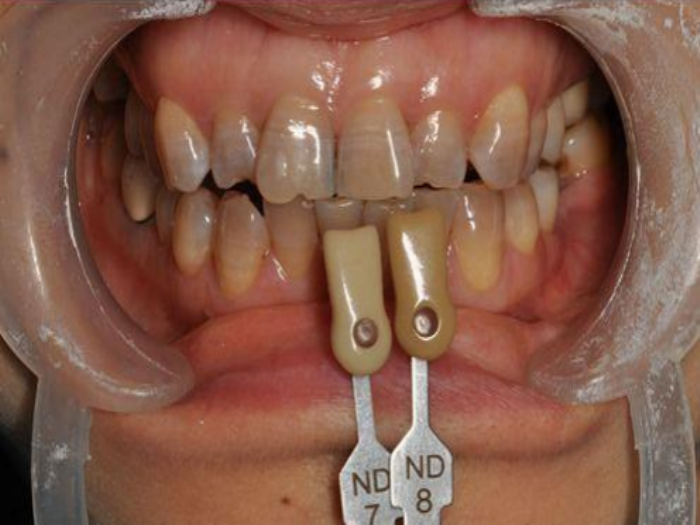

二、内源性着色

四环素牙,四环素是一类治疗细菌感染的药物,对发育中的牙齿具有染色作用,从前医学界没有重视到四环素对牙齿的染色作用,现在这类药物已经不用于儿童和孕妇了,但是仍有父母缺少这方面的知识,盲目应用四环素类药物,所以目前在儿童中仍可见四环素牙。这种病虽然称为四环素牙,但实际上不仅是四环素可以引起,像土霉素、金霉素、去甲金霉素等药物也可引起四环素牙,因为这些药物的结构与四环素相似,在医学上同属四环素药物家族。这其中四环素和去甲金霉素引起变色的作用最强。它们破坏牙齿是在牙齿发育的矿化期间产生的,这时进入人体的四环素与牙齿中的钙相结合,形成稳定的物质,影响牙体硬组织的矿化,引起牙釉质发育不全。